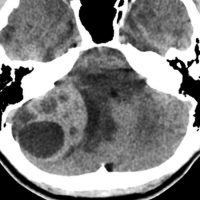

- CTでは小脳より白っぽい灰色(高密度)に写ります

この例は,小脳半球にできたものです。のう胞(水たまり)を形成しています。髄芽腫の大きな特徴は,造影剤を入れないCT(左側)で腫瘍が少し白く見えることです(灰白質より高密度といいます)。細胞密度が高いので高密度になります。この例はclassic medulloblastomaですが,MIB-1は45%に達するもので,急激な腫瘍発育を示します。